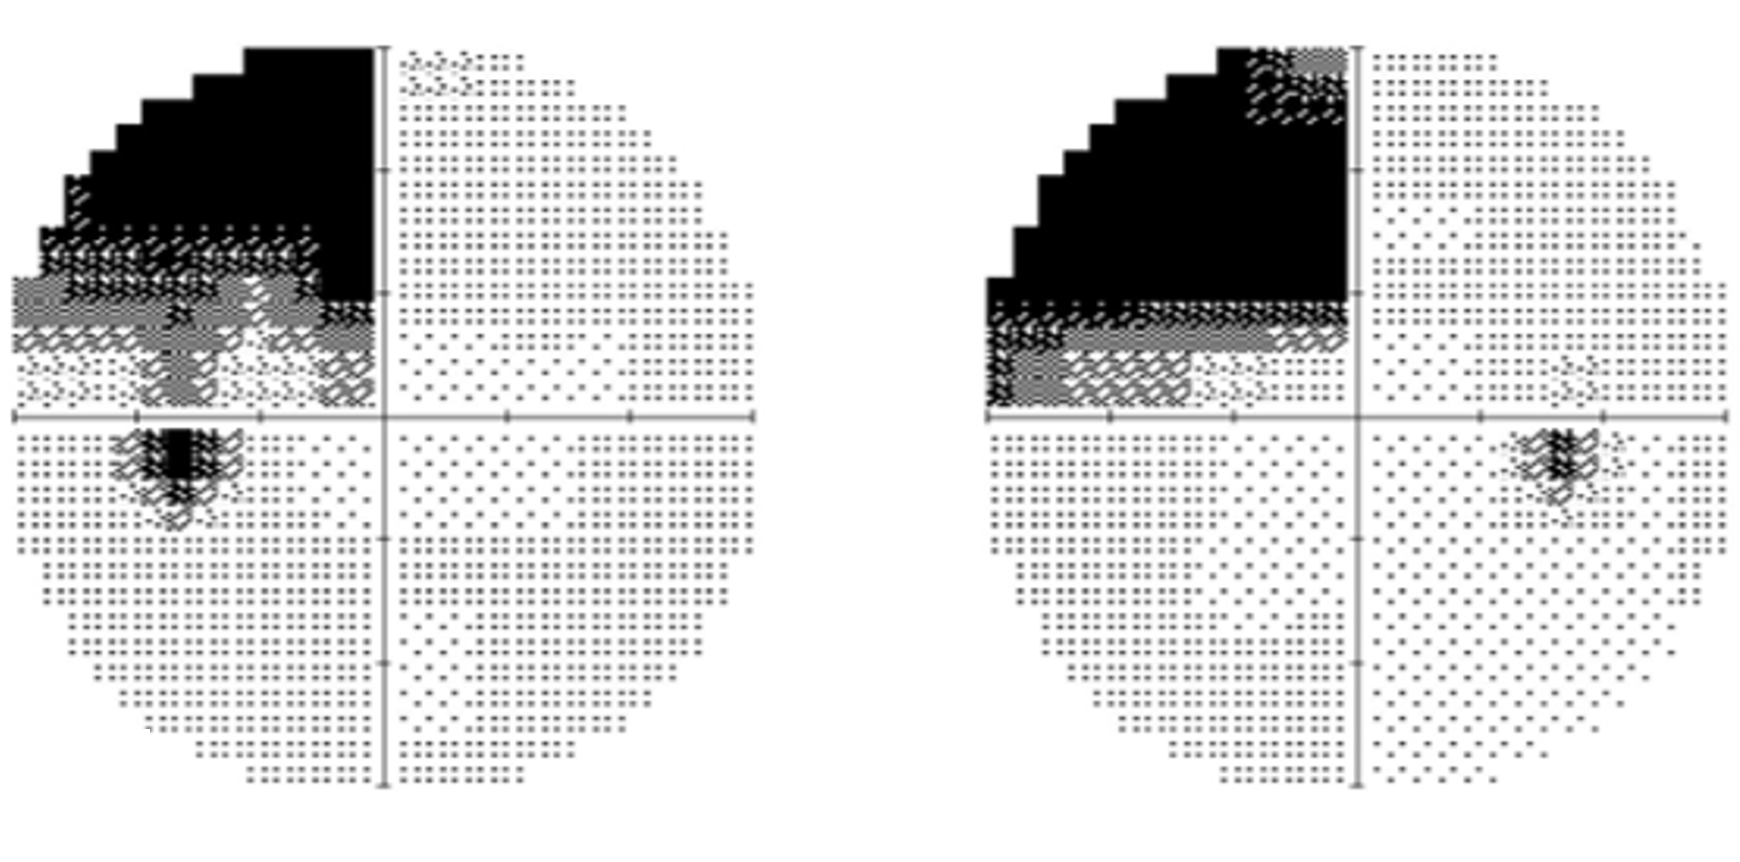

More info30-2 SITA-Fast visual field

Case 4: Right homonymous hemianopia

A 49 year old Asian male who has noticed recent difficulties reading. His best corrected visual acuity is 6/7.5 (20/25) in each eye. No RAPD is noted.

Given the clinical presentation below, this patient was referred promptly for neurological assessment to rule out a cortical lesion.